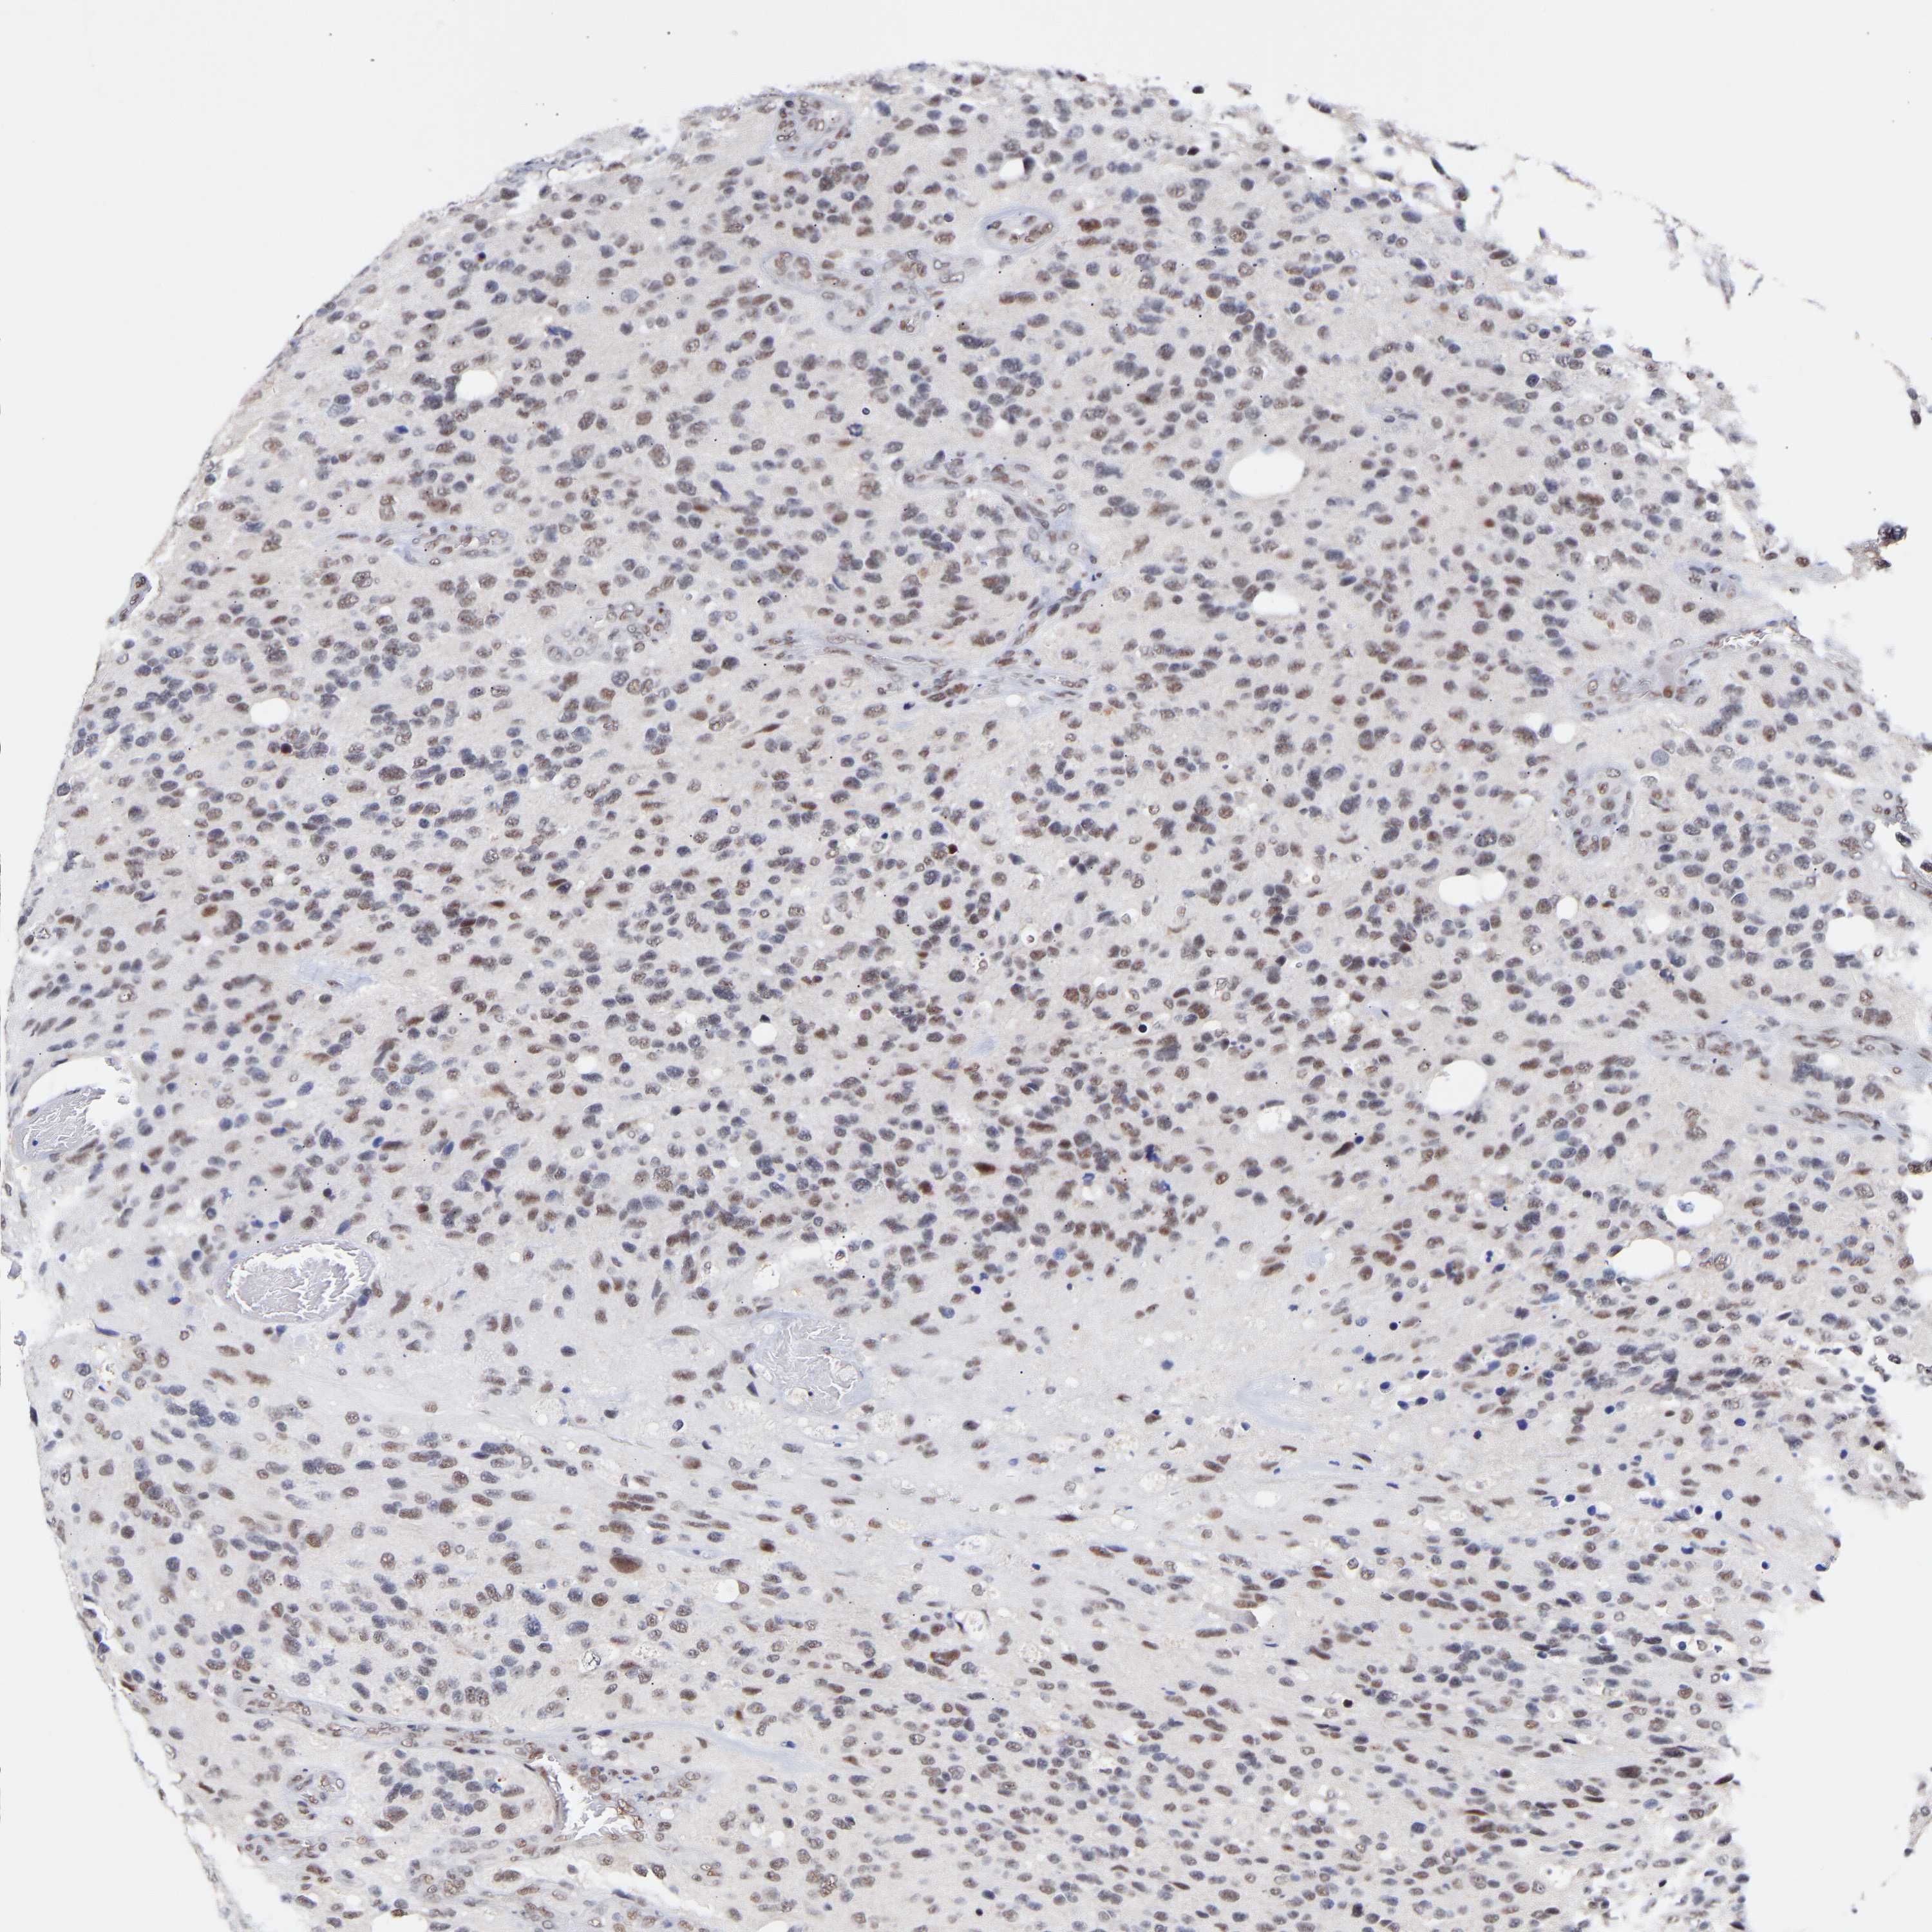

GLIOMA - Protein expressioni

A mouse-over function shows sample information and annotation data. Click on an image to view it in a full screen mode. Samples can be filtered based on level of antibody staining by selecting one or several of the following categories: high, medium, low and not detected. The assay and annotation is described here.

Note that samples used for immunohistochemistry by the Human Protein Atlas do not correspond to samples in the TCGA dataset.

Antibody stainingi

Antibody staining in the annotated cell types in the current human tissue is reported as not detected, low, medium, or high, based on conventional immunohistochemistry profiling in selected tissues. This score is based on the combination of the staining intensity and fraction of stained cells.

Each image is clickable and will lead to virtual microscopy that enables deeper exploration of all samples and also displays staining intensity scores, fraction scores and subcellular localization as well as patient and tissue information for each sample.

Antibody HPA019824

Antibody CAB015201

Staining

High

Medium

Low

Not detected

Intensity

Strong

Moderate

Weak

Negative

Quantity

>75%

75%-25%

<25%

None

Location

Nuclear

Cytoplasmic/membranous

Cytoplasmic/membranous,nuclear

Glioma, malignant, High grade

Glioma, malignant, Low grade